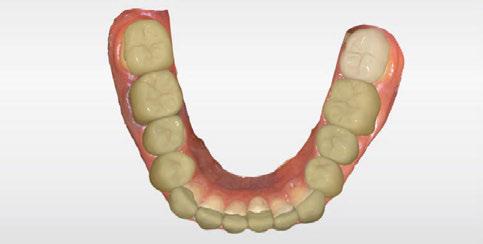

dentarias, cumpliendo parámetros biológicos, terapéuticos, mecánicos y estéticos. Después se realizó un modelado digital retrospectivo (Figuras 7-11) para generar modelos impresos 3D para realizar el mock up funcional, estético y como guía para las preparaciones (Figuras 12-15). Con ello, se efectuaron las preparaciones dentarias y los registros intermaxilares y, posteriormente, se digitalizaron ambos maxilares (Figuras 16-21)

SW 5.2, Dentsply Sirona) (Figuras 22-27), la cual fue materializada en dos tipos de materiales a partir de bloques cerámicos IPS Empress CAD y cerámica vítrea de disilicato de litio IPS E.max CAD (Figuras 28-30)

Figura 5. Impresión digital, vista superior derecha. Figura 3. Escaneado maxilar superior zona anterior. Figura 4. Impresión digital, vista superior izquierda.

Figura 6. Impresión digital, vista oclusal, maxilar inferior.

Figura 7. Modelado digital. Figura 9. Propuesta de diseño en oclusión Figura 10. Vista lateral derecha. Figura 8. Propuesta de diseño arcada superior. Figura 11. Vista oclusal superior del modelado. Figura 12. Mock Up impreso en oclusión. Figura 14. Mock Up que evidencia el desgaste dentario en el maxilar inferior.

Figura 13. Mock Up maxilar superior.

Figura 17. Digitalización maxilar superior e inferior. Figura 18. Digitalización maxilar inferior. Figura 15. Mock Up completo los dientes inferiores Figura 16. Preparaciones y registros interoclusales. Figura 19. Vista lateral, modelo digital inferior. Figura 20. Vista oclusal, modelo digital inferior.

Figura 25. Vista oclusal del diseño de las restauraciones en maxilar inferior. Figura 24. Diseño digital de las restauraciones maxilar inferior, vista frontal. Figura 21. Uso del Mock up para la determinación del registro intermaxilar. Figura 23. Diseño en oclusión, vista lateral. Figura 22. Diseño en oclusión. Vista frontal. Figura 26. Diseño digital de las restauraciones.

Figura 27. Diseño de las restauraciones en oclusión.

Figura 30. Restauracones impresas vista oclusal superior e inferior. Figura 29. Prueba de las restauraciones en modelo impreso en 3D. Figura 28. Bloques de IPS Empress CAD fresados. Vista frontal.

Figura 33. Vista oclusal superior. Figura 34. Vista oclusal maxilar Inferior. Figura 31. Restauraciones cementadas, vista anterior superior. Figura 32. Restauraciones cementadas, vista anterior inferior. Figura 35. Vista en oclusión del caso terminado.